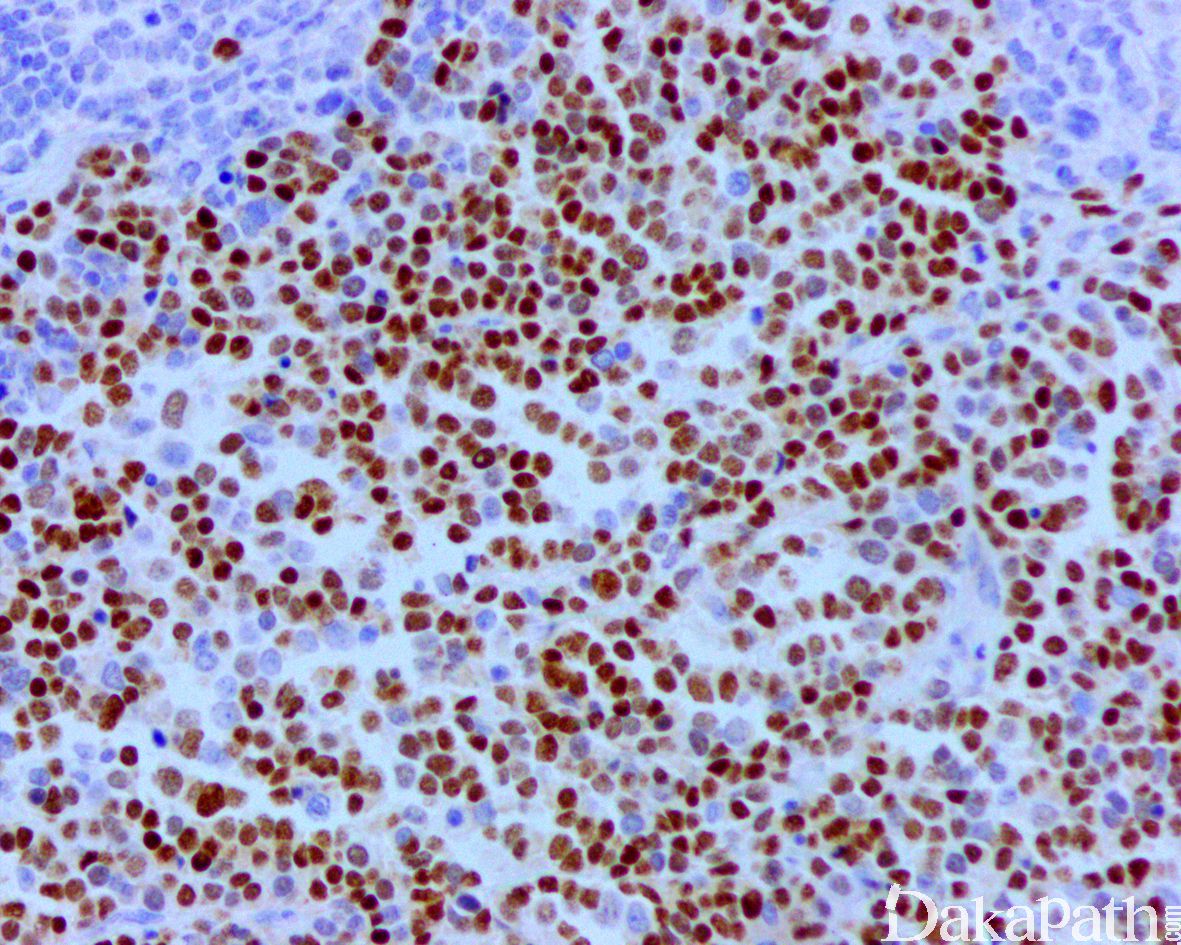

免疫组织化学染色:

desmin、MSA、myogenin 和 MyoD1 常阳性。Myogenin 通常为强而弥漫的阳性。伴有 PAX3/7-FOXO1 基因易位的腺泡状横纹肌肉瘤常表达 OLIG2. 部分病例可表达 CK(尤其是发生于头颈部者)以及神经内分泌标志物(特别是 CD56 和 Syn,通常不表达 CGA)可误诊为神经内分泌癌。

预后差,常见肺和淋巴结转移;弥漫表达 Myogenin 者较局灶表达着预后更差,实体型较经典型预后差,